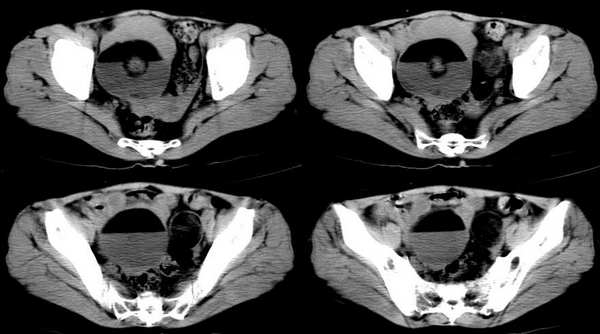

女,55岁,因下腹胀痛2月,b超发现盆腔包块7天,而入院,检查:右侧附件如女拳头大小包块,活动差,轻压痛,质中,子宫稍正常缩小,彩超示子宫4.9cmx2.6cmx2.3cm ,右侧附件包块示:8.7cmx9.1cmx6.3cm 的混合性回声,脂质分层征

囊性畸胎瘤的液-液征,增强瘤结节强化。

畸胎瘤伴瘤内出血。

双侧卵巢畸胎瘤,右侧为著

畸胎瘤(两侧)

双侧卵巢畸胎瘤

畸胎瘤,可见典型脂肪-液体征象。

同意大家畸胎瘤的诊断,但不能排除恶变的可能.

右侧肿块前壁的带状软组织密度影我认为是肠管所致,该部位的小肠肠襻由于受到肿瘤的推移呈水平样排列,这样在ct扫描时相邻的肠壁在某些层面上可以呈现宽带状软组织密度影。

良性畸胎瘤伴出血。

畸胎瘤,脂-液分层